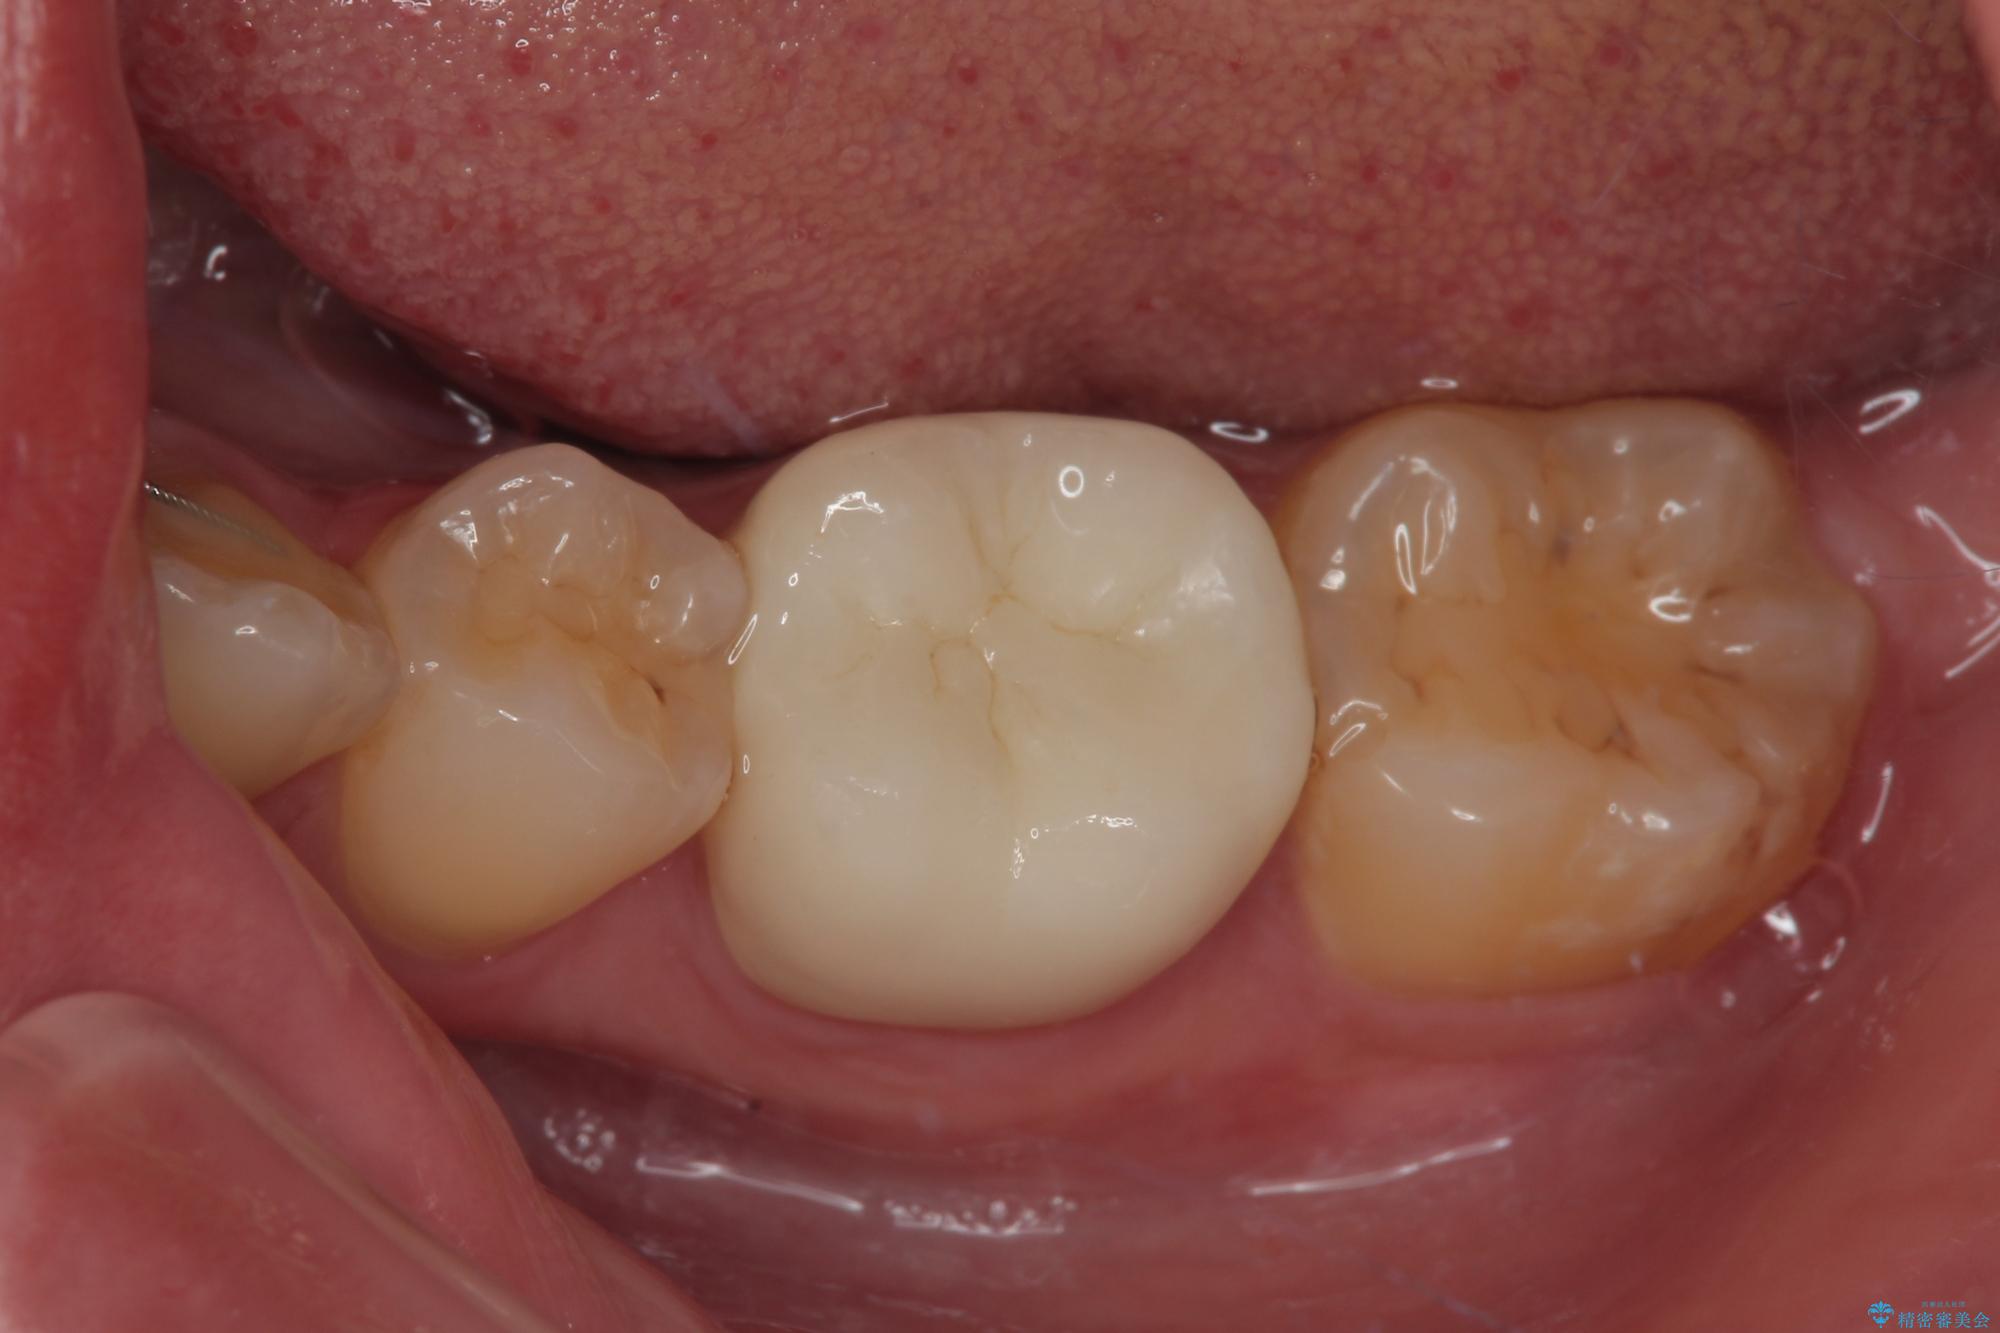

- 当院で矯正治療を終えて、左下が虫歯になっている気がするとのことで来院された患者様です。レントゲン検査の結果、コンポジットレジンによる修復箇所が複数行われており、詰め物の下に虫歯を認めました。

拡大鏡視野下でコンポジットレジン、虫歯の除去を行い、オールセラミッククラウンに適した形に整えました。

歯と歯茎の間に圧排糸と言われる糸を入れてシリコーン印象材にて精密な型どりをしました。

虫歯による不快な症状がなくなり喜んでいただきました。セラミックの被せものが入った後の違和感なく過ごせているそうです。矯正治療終了直後の被せもの治療なのでリテーナーの作成回数をできるだけ少なく迅速に行うことを考慮して治療を行いました。

今後、ホワイトニングを行う予定なので、患者様のご希望により、周りの歯に比べてあえて白い被せものを作成しました。